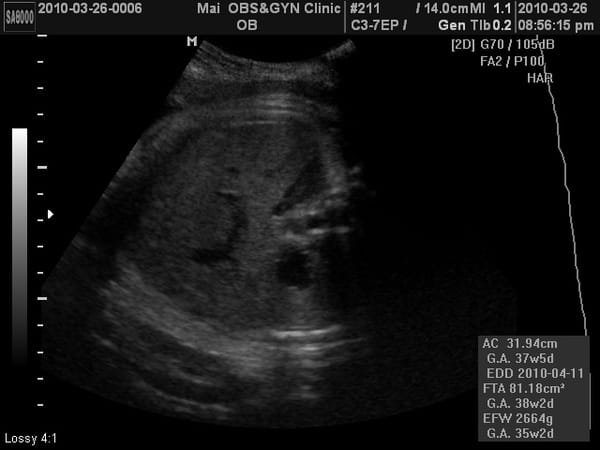

這次又看得到4D照了,相當有肉,臉頰有肉、鼻子有肉、嘴巴也很有肉、連胸部也擠出一團肉~~~

我一直說可能是因為頭在下被擠壓的關係,所以看起來很有肉啦~不過M醫生卻沒有回我話。